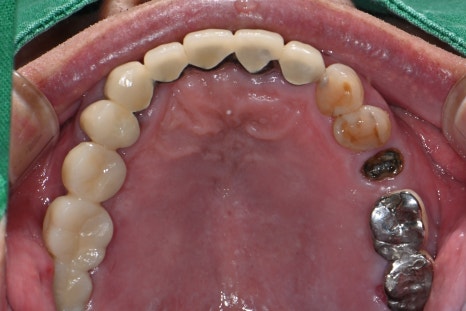

-After treatment

Left image: A panoramic X-ray taken after completion of the #25-27 prosthesis.

Right image: The prosthesis was finished with zirconia that is aesthetic and durable, like natural teeth.